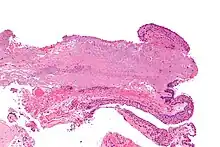

Micrograph of a conjunctiva associated with prominent blood vessels (left-bottom of image) and elastotic collagen (centre of image), as may be seen in a pterygium. H&E stain.

Pterygium in the conjunctiva is characterized by elastotic degeneration of collagen (actinic elastosis[12]) and fibrovascular proliferation. It has an advancing portion called the head of the pterygium, which is connected to the main body of the pterygium by the neck. Sometimes a line of iron deposition can be seen adjacent to the head of the pterygium called Stocker's line. The location of the line can give an indication of the pattern of growth.